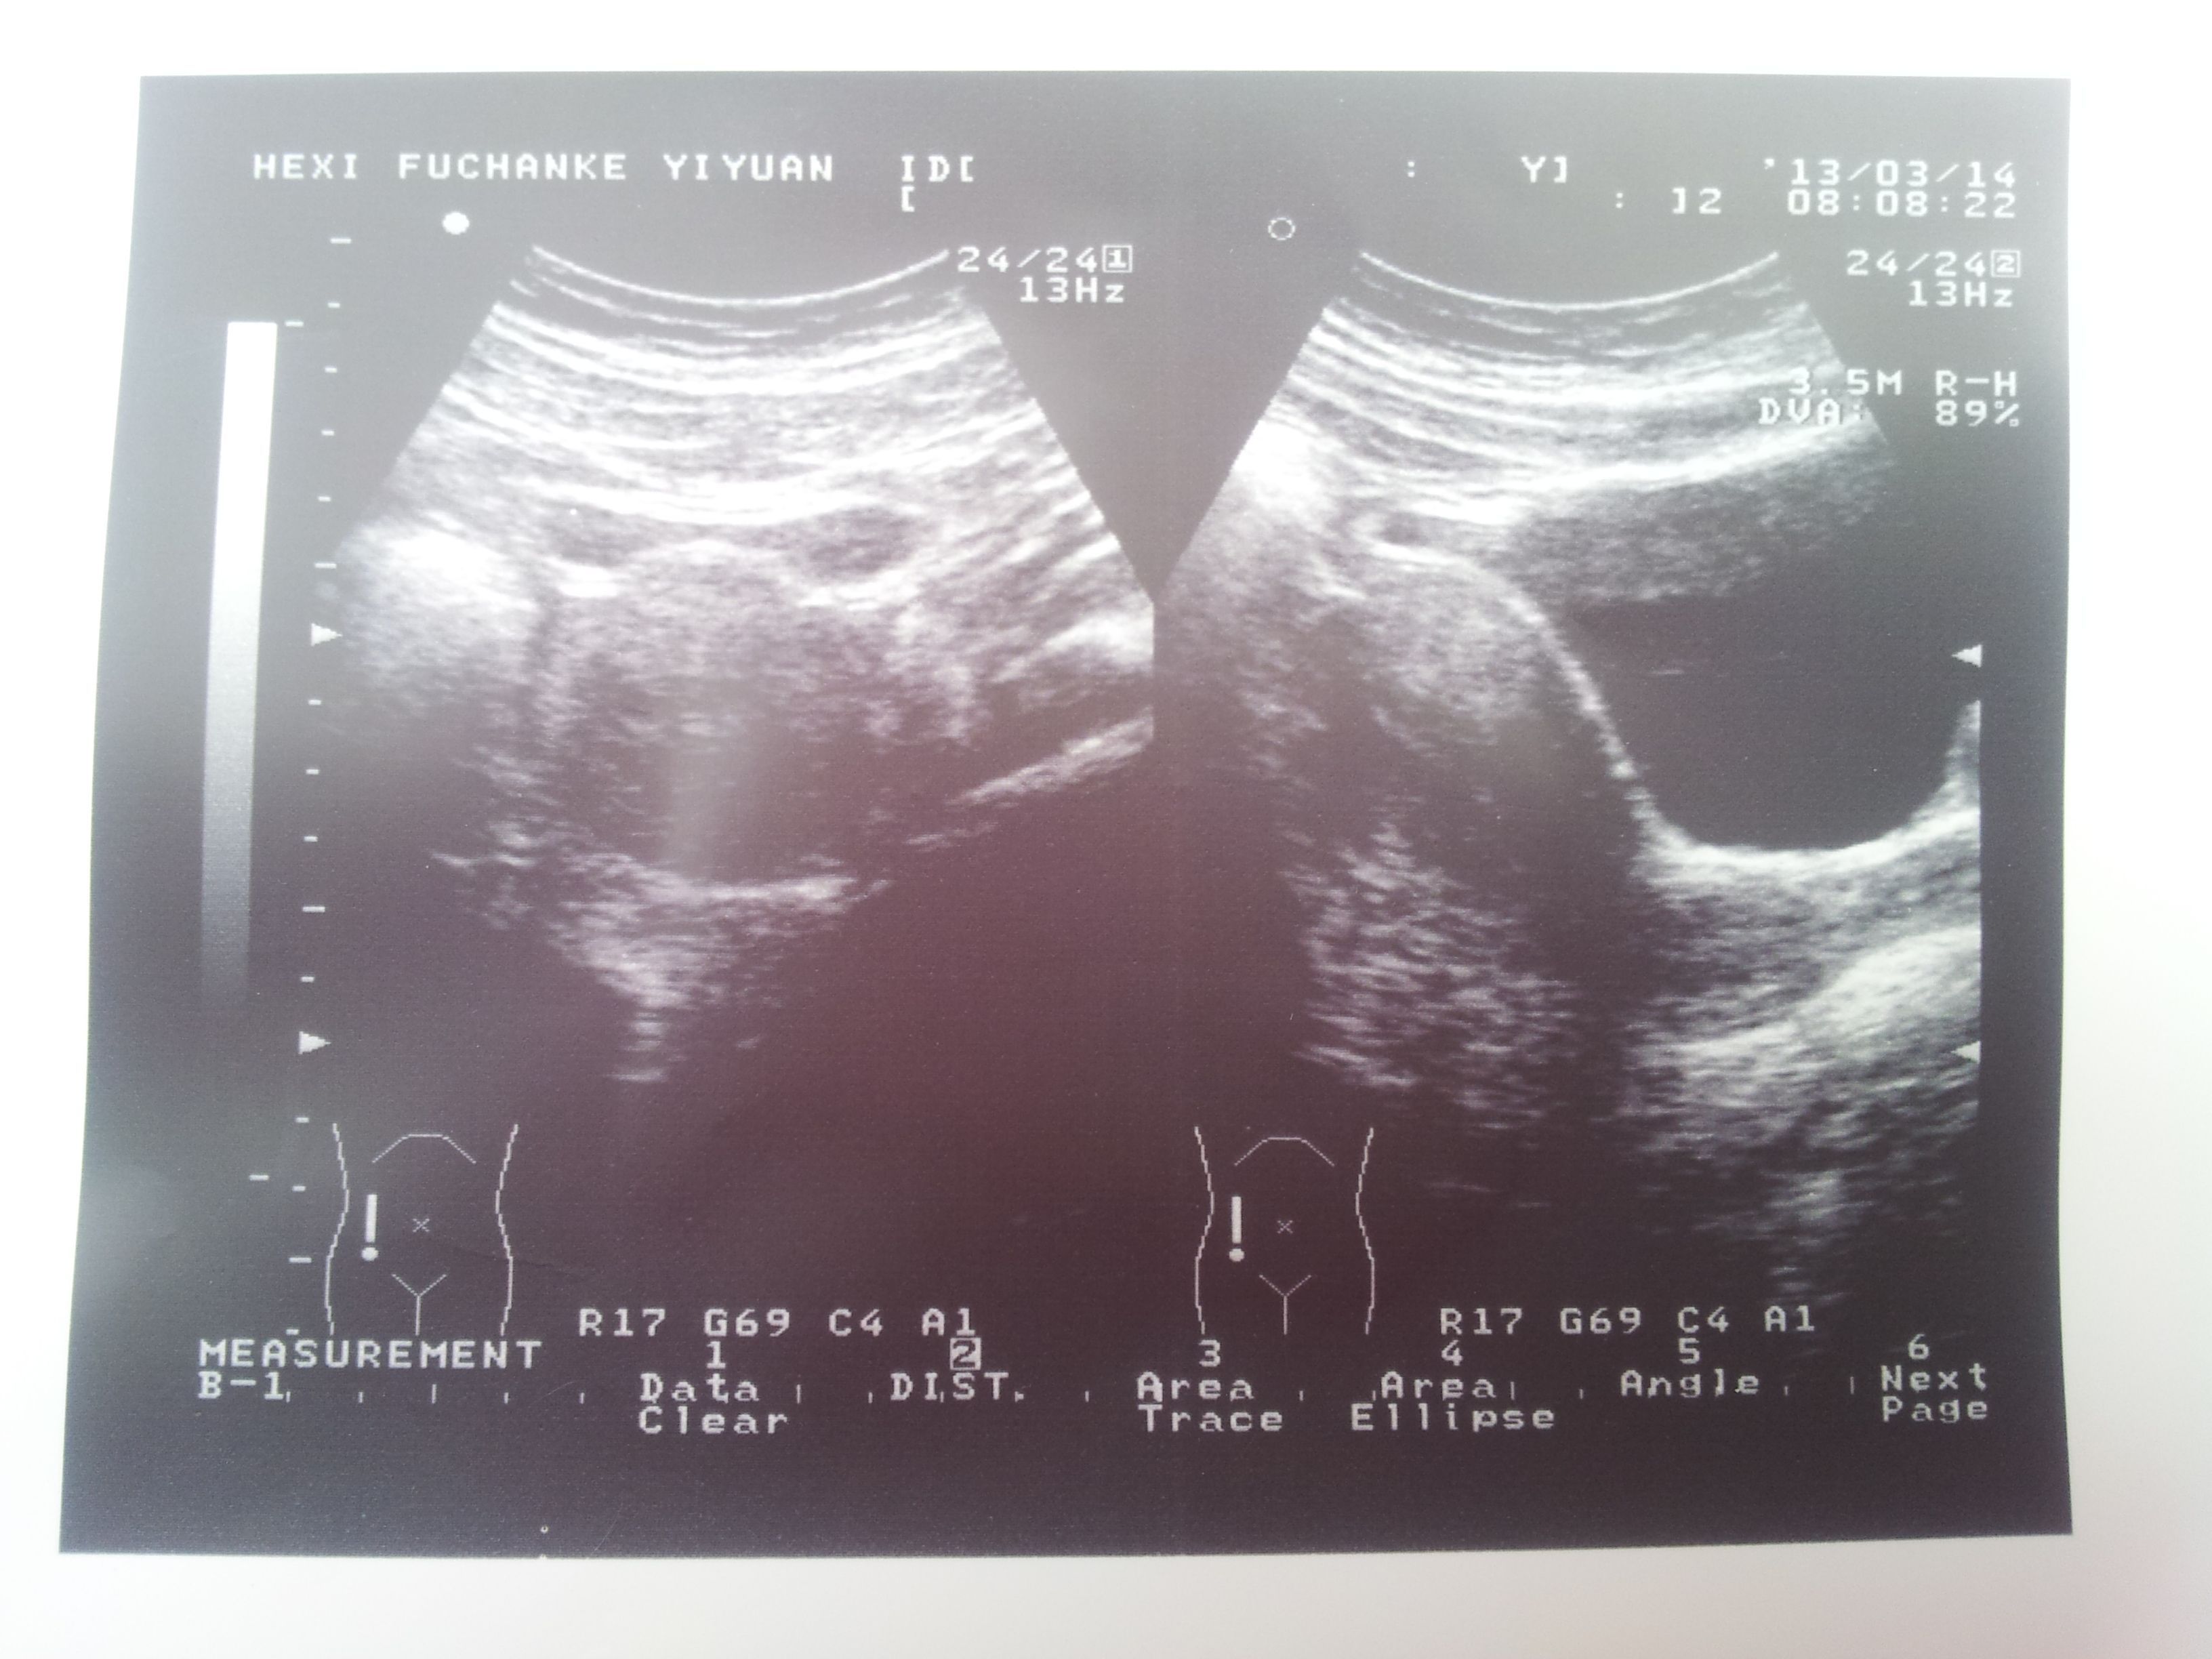

有懂得帮我看看么 心理很害怕 我是做孕前检查发现的

因为是免费检查,所以大夫不跟我说特别清楚。说叫我做进一步检查。而且说我子宫大,叫我查明原因。。我妈妈说她子宫口也大,但是照样样顺产生的我。。可是就是不知道那个异物是什么了、、、图片不太清楚,因为我准备要孩子,出现这个问题里。心里很害怕。希望懂的人帮我看看,或者告诉我下一步应该做什么检查!

不必担心,目前怀疑是子宫肌瘤。可做彩超再查查。看不清包块的单位是什么,不太大的可能不影响受孕。